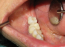

Implants

This page contains examples of only a few of the cases which our office have completed over the past 38+ years.